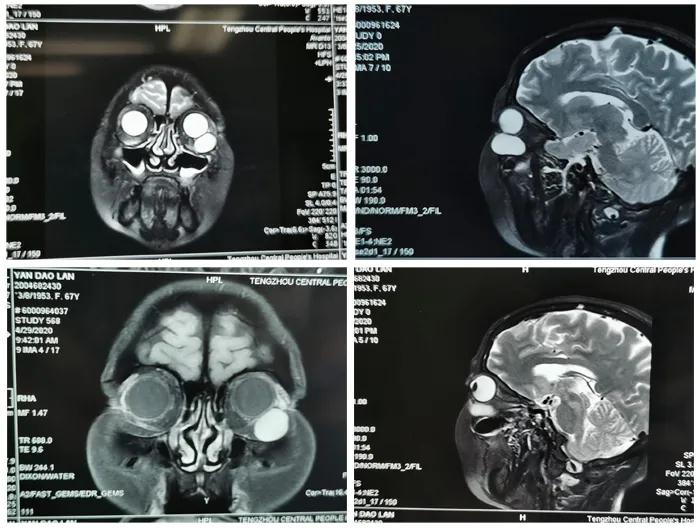

患者,女,65歲。因“發(fā)現(xiàn)左眼眶內(nèi)腫物3月”于5月24日收入眼二科病房。入院行眼眶CT、MRI檢查,術(shù)前閱片發(fā)現(xiàn)該患者左眼眶內(nèi)腫物,體積大,位置較深,邊界清,直徑約3.0cm類圓型腫物,與下直肌有粘連。

5月26日,患者在全麻下行前路開眶摘除左眼眶內(nèi)腫物。手術(shù)過程順利,僅用一個(gè)小時(shí)完成手術(shù)。術(shù)后患者眼球運(yùn)動(dòng)良好,無復(fù)視癥狀,眼外肌無損傷,視力無下降,眶下神經(jīng)無損傷,無任何手術(shù)并發(fā)癥,患者及家屬表示非常滿意。病理結(jié)果回報(bào)海綿狀血管瘤?,F(xiàn)患者康復(fù)出院。